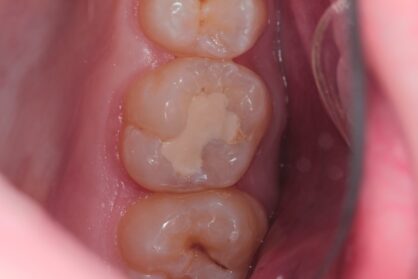

Приклади робіт лікаря-стоматолога

Естетична реставрація. До / після